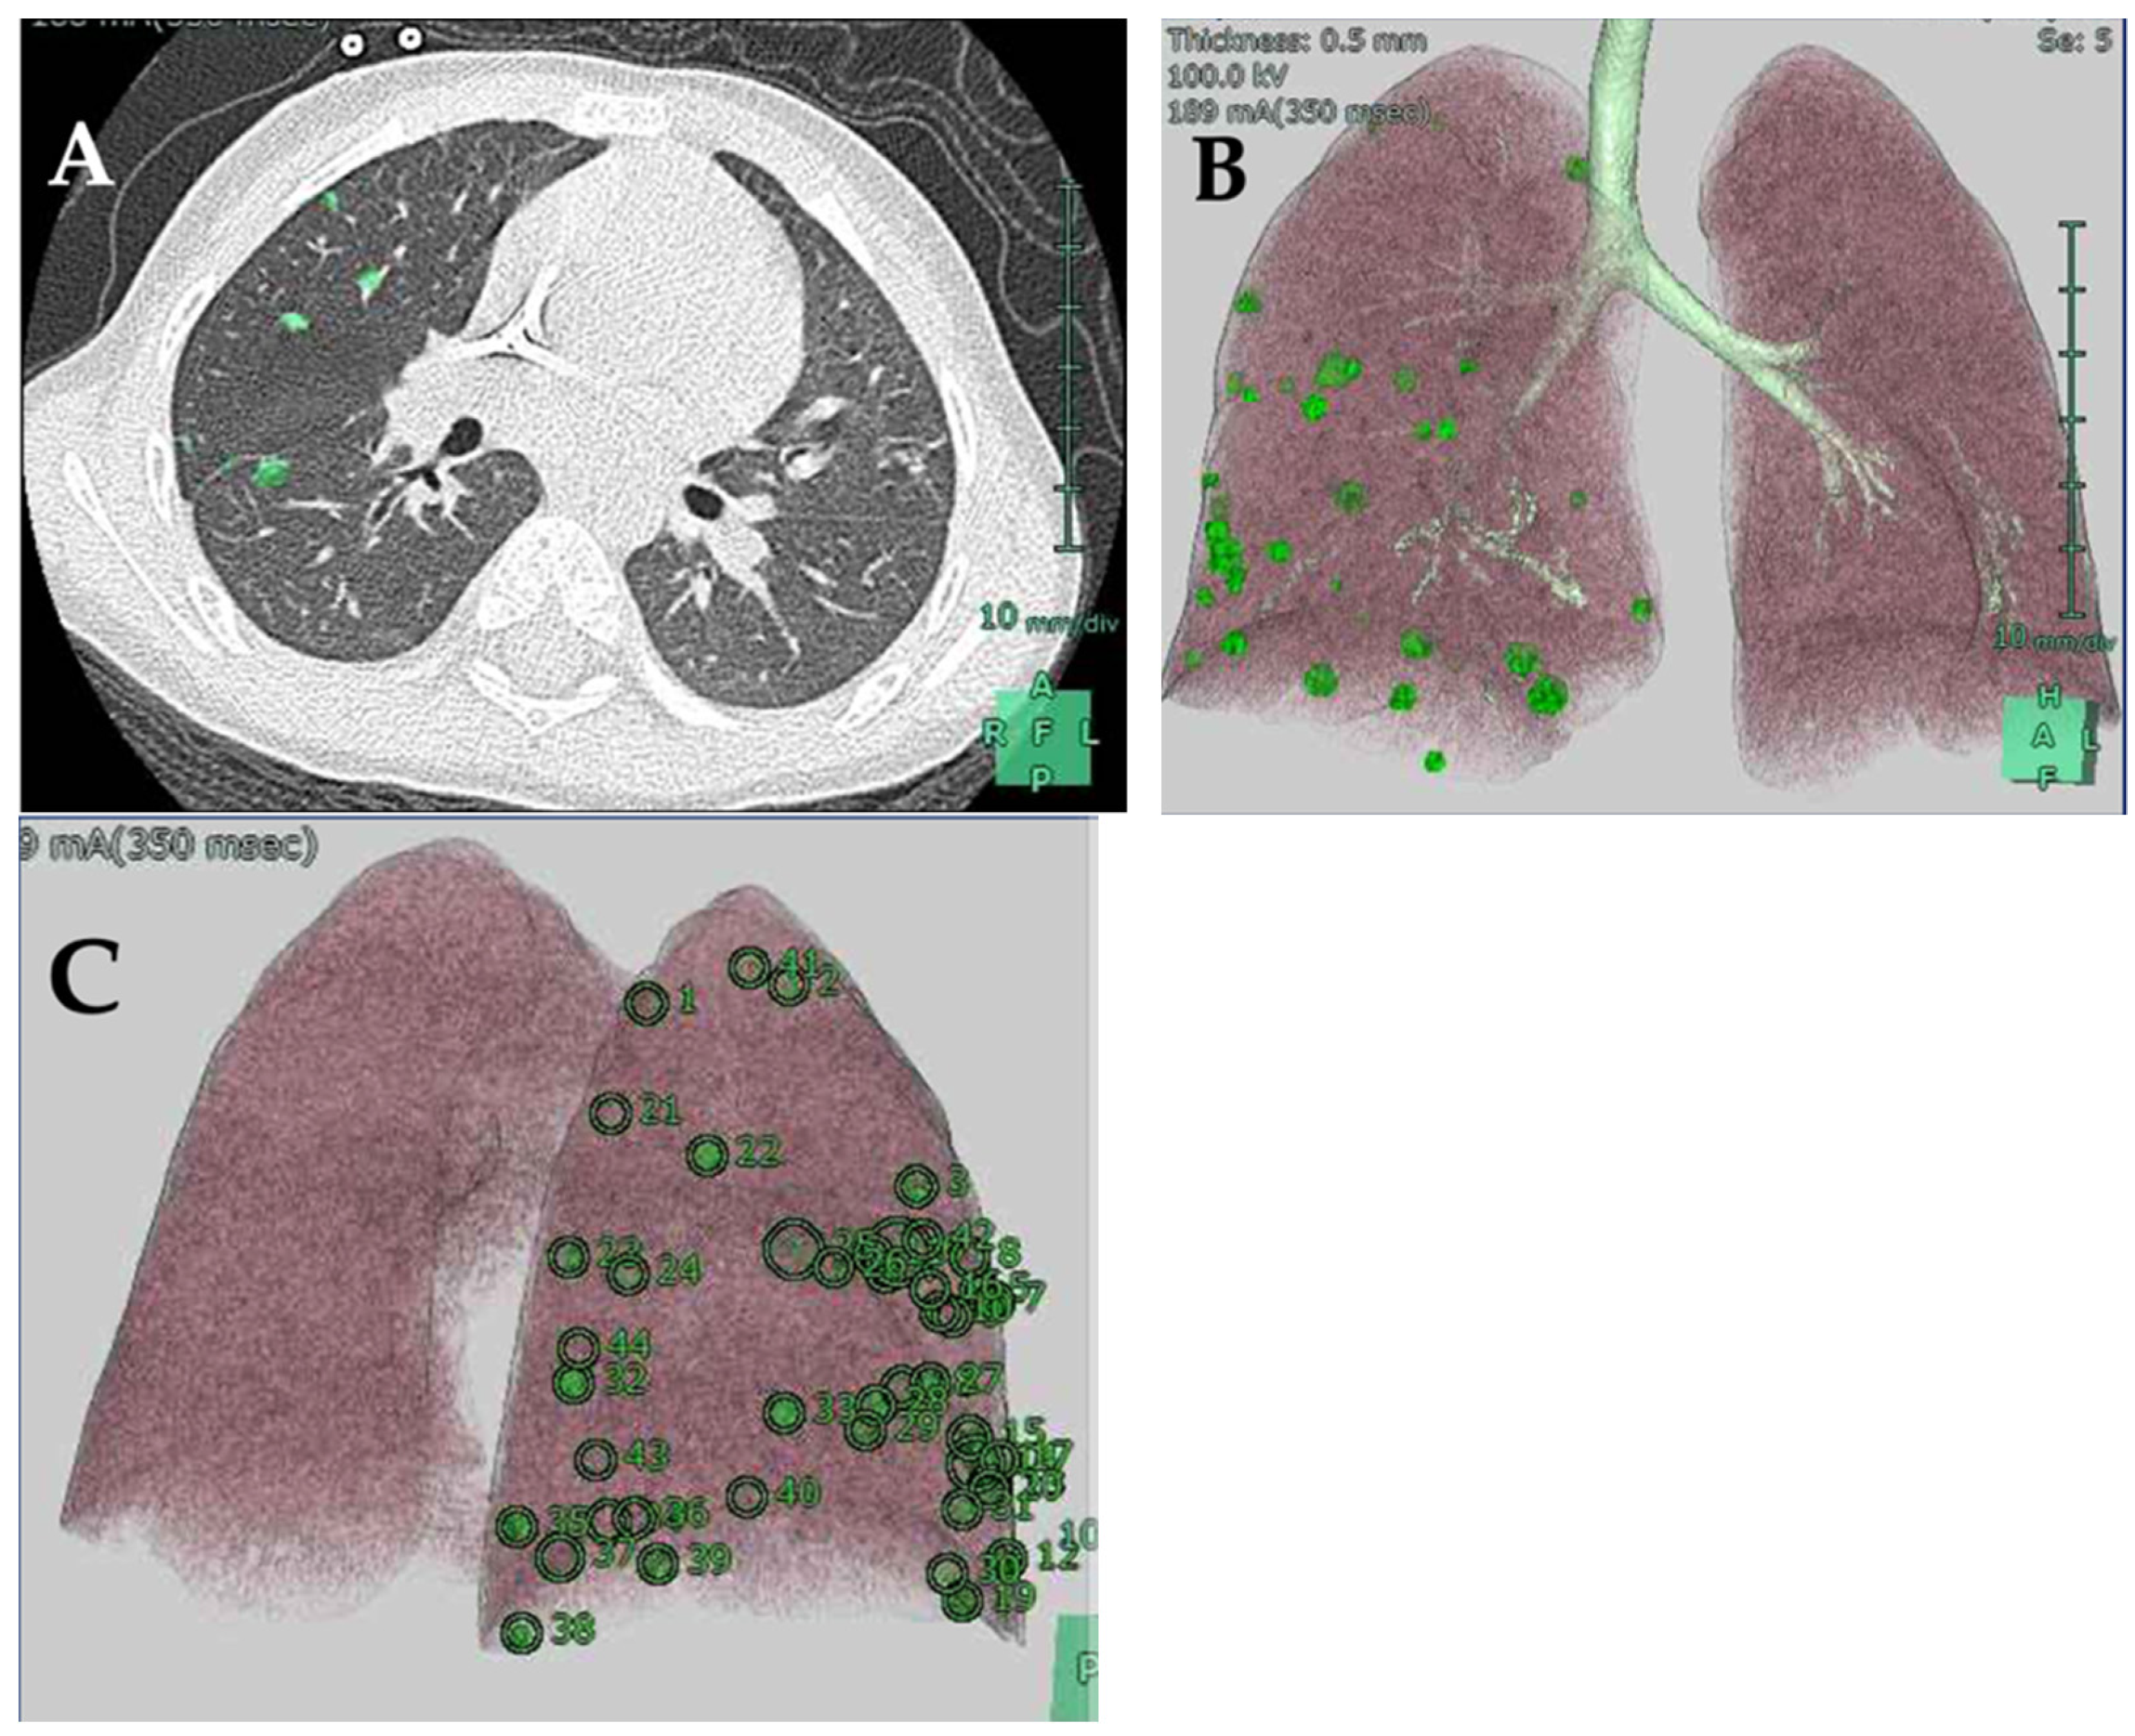

2. Case Report